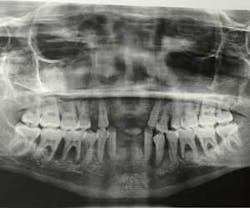

A 17-year-old, African American female, well nourished and otherwise healthy, was referred for bone loss associated with teeth Nos. 21, 22, 23, 24, 25, 27, and 28 (figures 1 and 2).

A panoramic radiograph (figure 8) and cone beam CT (CBCT) scan were obtained for evaluation of alveolar bone height and width and all sinus and mental foramen positions.